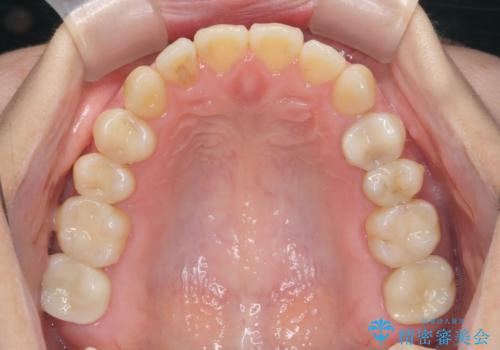

銀歯をゼロに! 短期間で行うメタルフリー治療

銀歯を丁寧に除去したのち、精度の良いセラミックインレー、セラミッククラウンで修復・補綴処置を行っていきます。

「長年気になっていた銀歯を全て除去し、気持ちが明るくなりました。」、と嬉しい感想をいただくことができました。